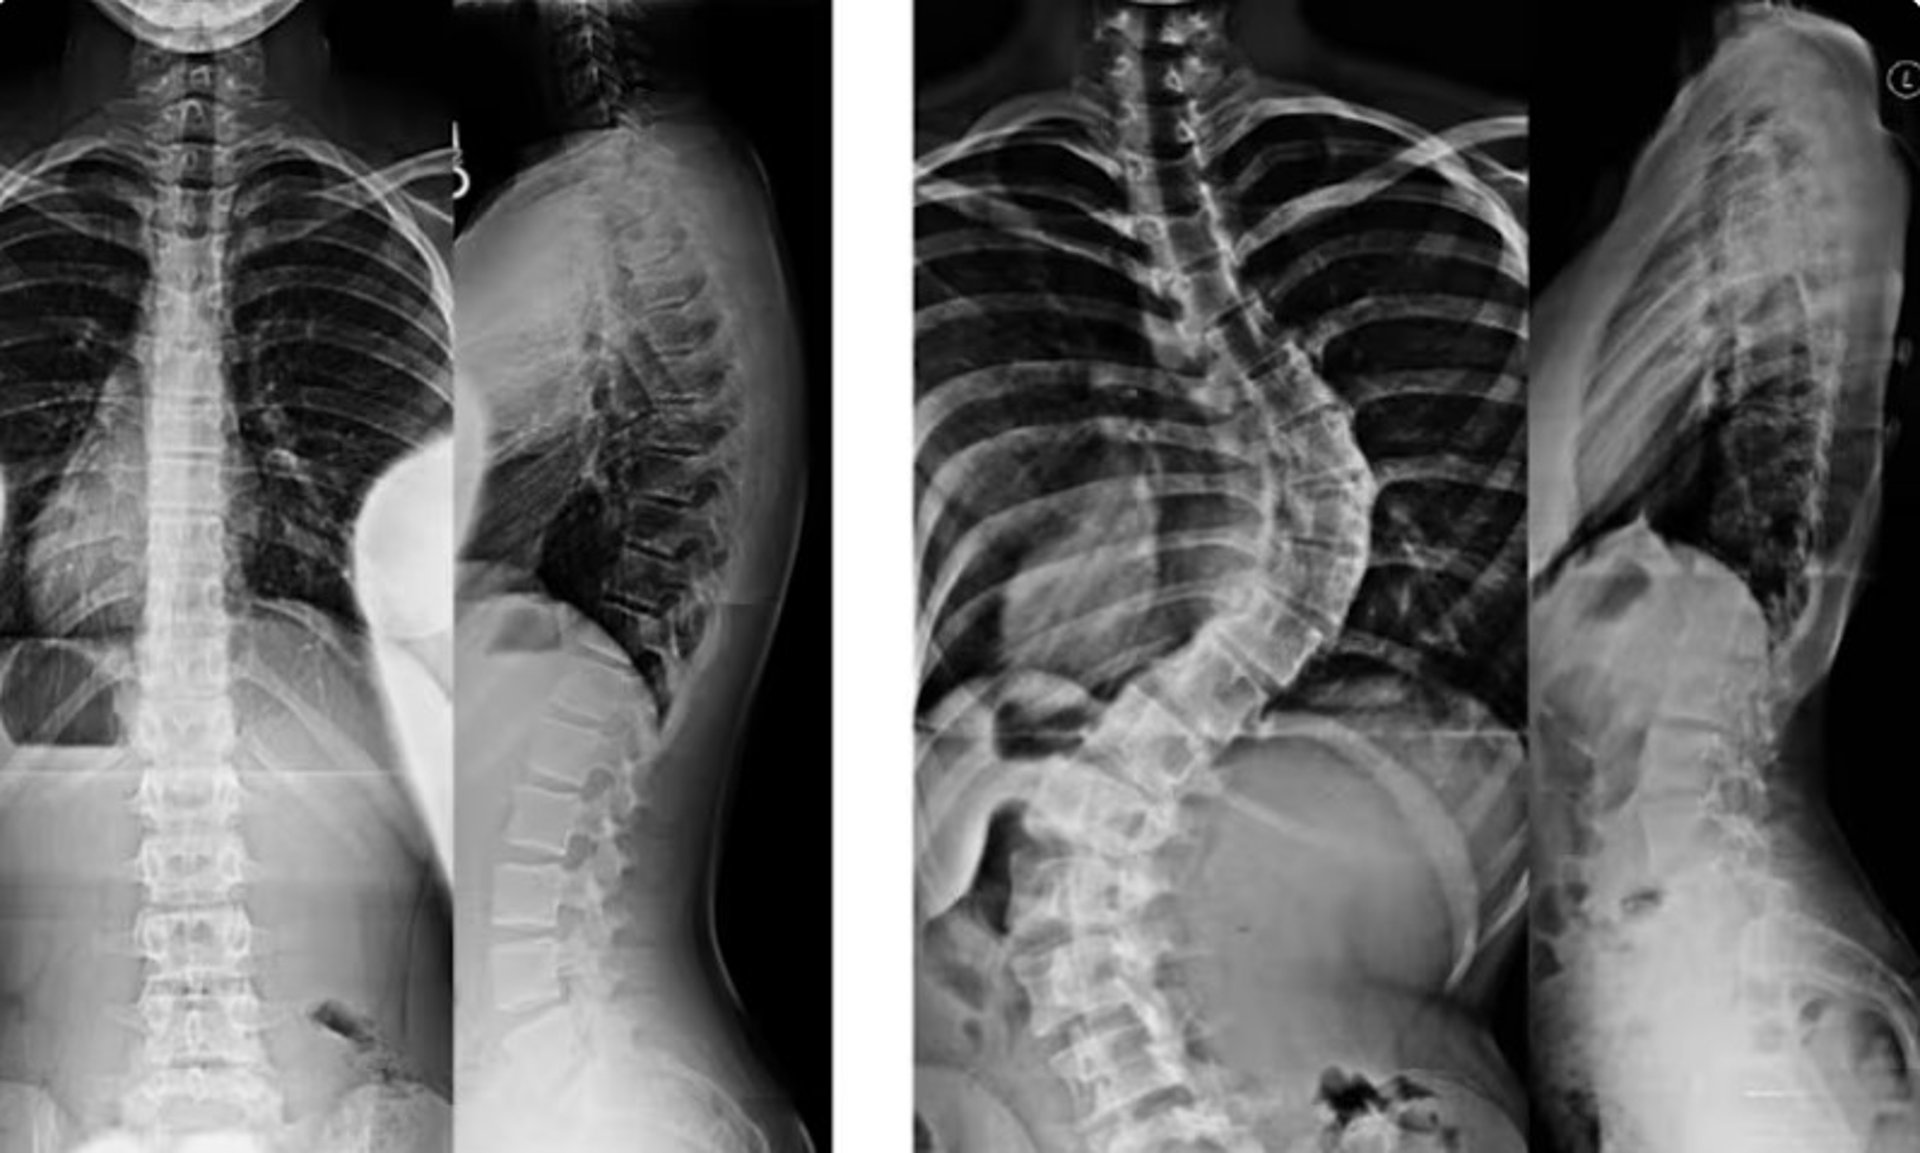

غالبًا ما يتطوّر الجنف بشكل تدريجي وقد لا يسبب ألمًا واضحًا في مراحله المبكرة. كثير من الأفراد — سواء الأطفال أو البالغين — قد لا يدركون إصابتهم بالجنف إلا بعد ملاحظة تغيّرات في وضعية الجسم أو وجود عدم تماثل واضح. ويساعد فهم العلامات الشائعة للجنف في تحديد ما إذا كان من المناسب إجراء تقييم مهني.

يؤثر الجنف على محاذاة العمود الفقري ووضعية الجسم. قد تستفيد أنت أو طفلك من إجراء تقييم إذا لاحظتم واحدًا أو أكثر من العلامات التالية:

عند الانحناء إلى الأمام (مثل ربط الحذاء)، قد يبدو أحد جانبي القفص الصدري أو أسفل الظهر أعلى أو أكثر بروزًا من الآخر — وهي علامة شائعة على دوران العمود الفقري المرتبط بالجنف.

تساعد هذه النتائج الموضوعية على تحديد ما إذا كان الجنف موجودًا، وطبيعة انحناء العمود الفقري، وما إذا كانت هناك حاجة إلى رعاية إضافية — مثل المتابعة الدورية، أو إعادة التأهيل، أو استخدام الدعّامات — وفقًا للحالة.